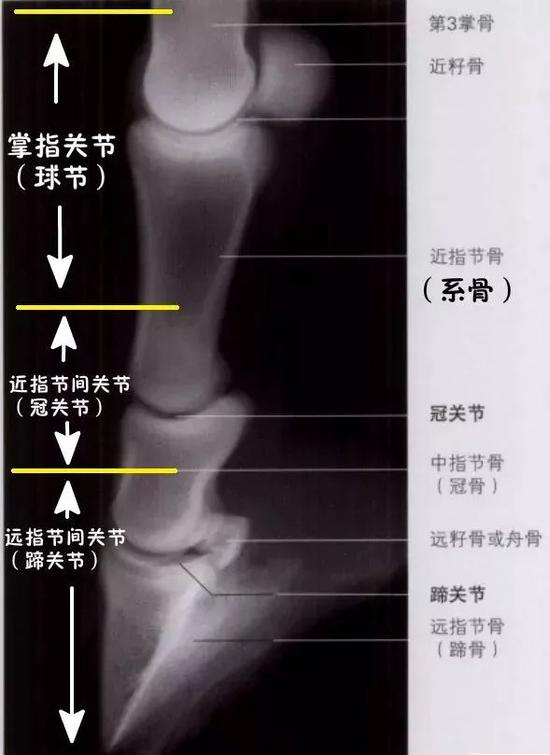

要记住球节,很简单,一句话:球节就是掌指关节,俗名叫“球节”,这么一俗不要紧导致很多人云里雾里,到底啥是球节?其实最近的的就是顾名思义,球节是掌指关节,指的就是掌骨和指骨之间的部分。

所以,只要知道掌骨和指骨,那中间的那部分就是掌指关节,也就是球节。

▲ 球节是掌指关节,就是掌骨和指骨之间的部分

2、马的系骨在哪里?

怎么记系骨呢?简单点,记住马的指骨=系骨+冠骨+蹄骨。也就是说,系骨是指骨的第一块长骨,如上图所示,因为是靠近身体一侧的,所以也叫近指骨。

球节下边的三大块骨头组成了指骨,第一个较长的那个就是系骨。

也就是说,球节下边的那个就是系骨。

▲ 球节下边的那个就是系骨